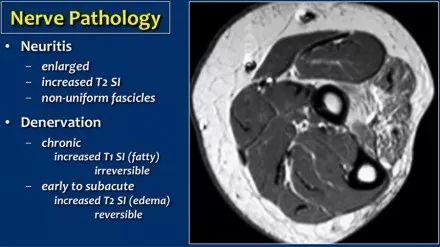

失神经支配:当神经炎或神经受压时,神经病理可表现为神经增厚。神经病理学的次要征象是肌肉水肿和/或萎缩的去神经支配。在这种情况下,T1上有高信号的慢性萎缩,这是不可逆转的。在早期或亚急性去神经支配中,突出的征兆是在T2W图像上具有高信号的水肿并且是可逆的。